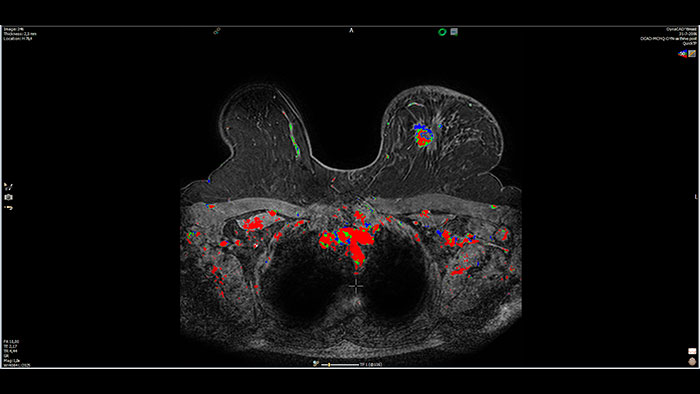

Next generation of breast care

Tailored to enhance the review and analysis of MRI breast studies by providing a flexible workspace with custom hanging protocols and multi-vendor** viewing capabilities. DynaCAD’s automatic segmentation allows on-the-fly user modification and provides volume analysis, lesion composition statistics, histograms, and a 3D rendered morphological overview.

Lesion characterization by reviewing vascular leakage

Designed to visualize T1 weighted DCE 3D datasets and assist in analyzing the tissue response.

Support in assessing lesions by reviewing blood supply characteristics

Designed to evaluate time intensity curves of a T1 signal enhancement series. The application produces measurements including relative enhancement, maximum enhancement, time to peak (TTP), and wash-in/wash-out rates.